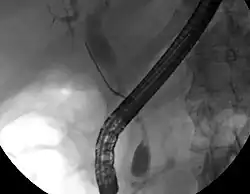

Bien que l'imagerie non invasive abdominale puisse se révéler utile dans l'établissement du diagnostic, l'imagerie locale des voies biliaires s'avère souvent nécessaire. La cholangio-pancréatographie rétrograde par voie endoscopique (CPRE, ou en anglais ERCP — ou cathétérisme endoscopique bilio-pancréatique) est une procédure combinant l'endoscopie et la fluoroscopie réalisée par un gastro-entérologue ou un chirurgien, largement utilisée dans ce but.

Bien qu'invasive et présentant des risques per- et post-opératoires (développement de pancréatite dans 5 % des cas, risques classiques inhérents à l'endoscopie), elle présente l'avantage de permettre un brossage pour examen cytologique, d'obtenir une biopsie et de placer un stent ou de procéder à d'autres interventions pour éliminer l'obstruction biliaire (dilatation des voies biliaires ou lyse d'une éventuelle lithiase)[10]. Une échographie endoscopique peut aussi être réalisée en même temps[60]. L'IRM au niveau pancréatique et biliaire est une alternative non-invasive à l'ERCP[61],[62],[63]. Certains auteurs ont suggéré que l'IRM pourrait supplanter l'ERCP dans le diagnostic des cancers biliaires[64],[65],[66],[67].